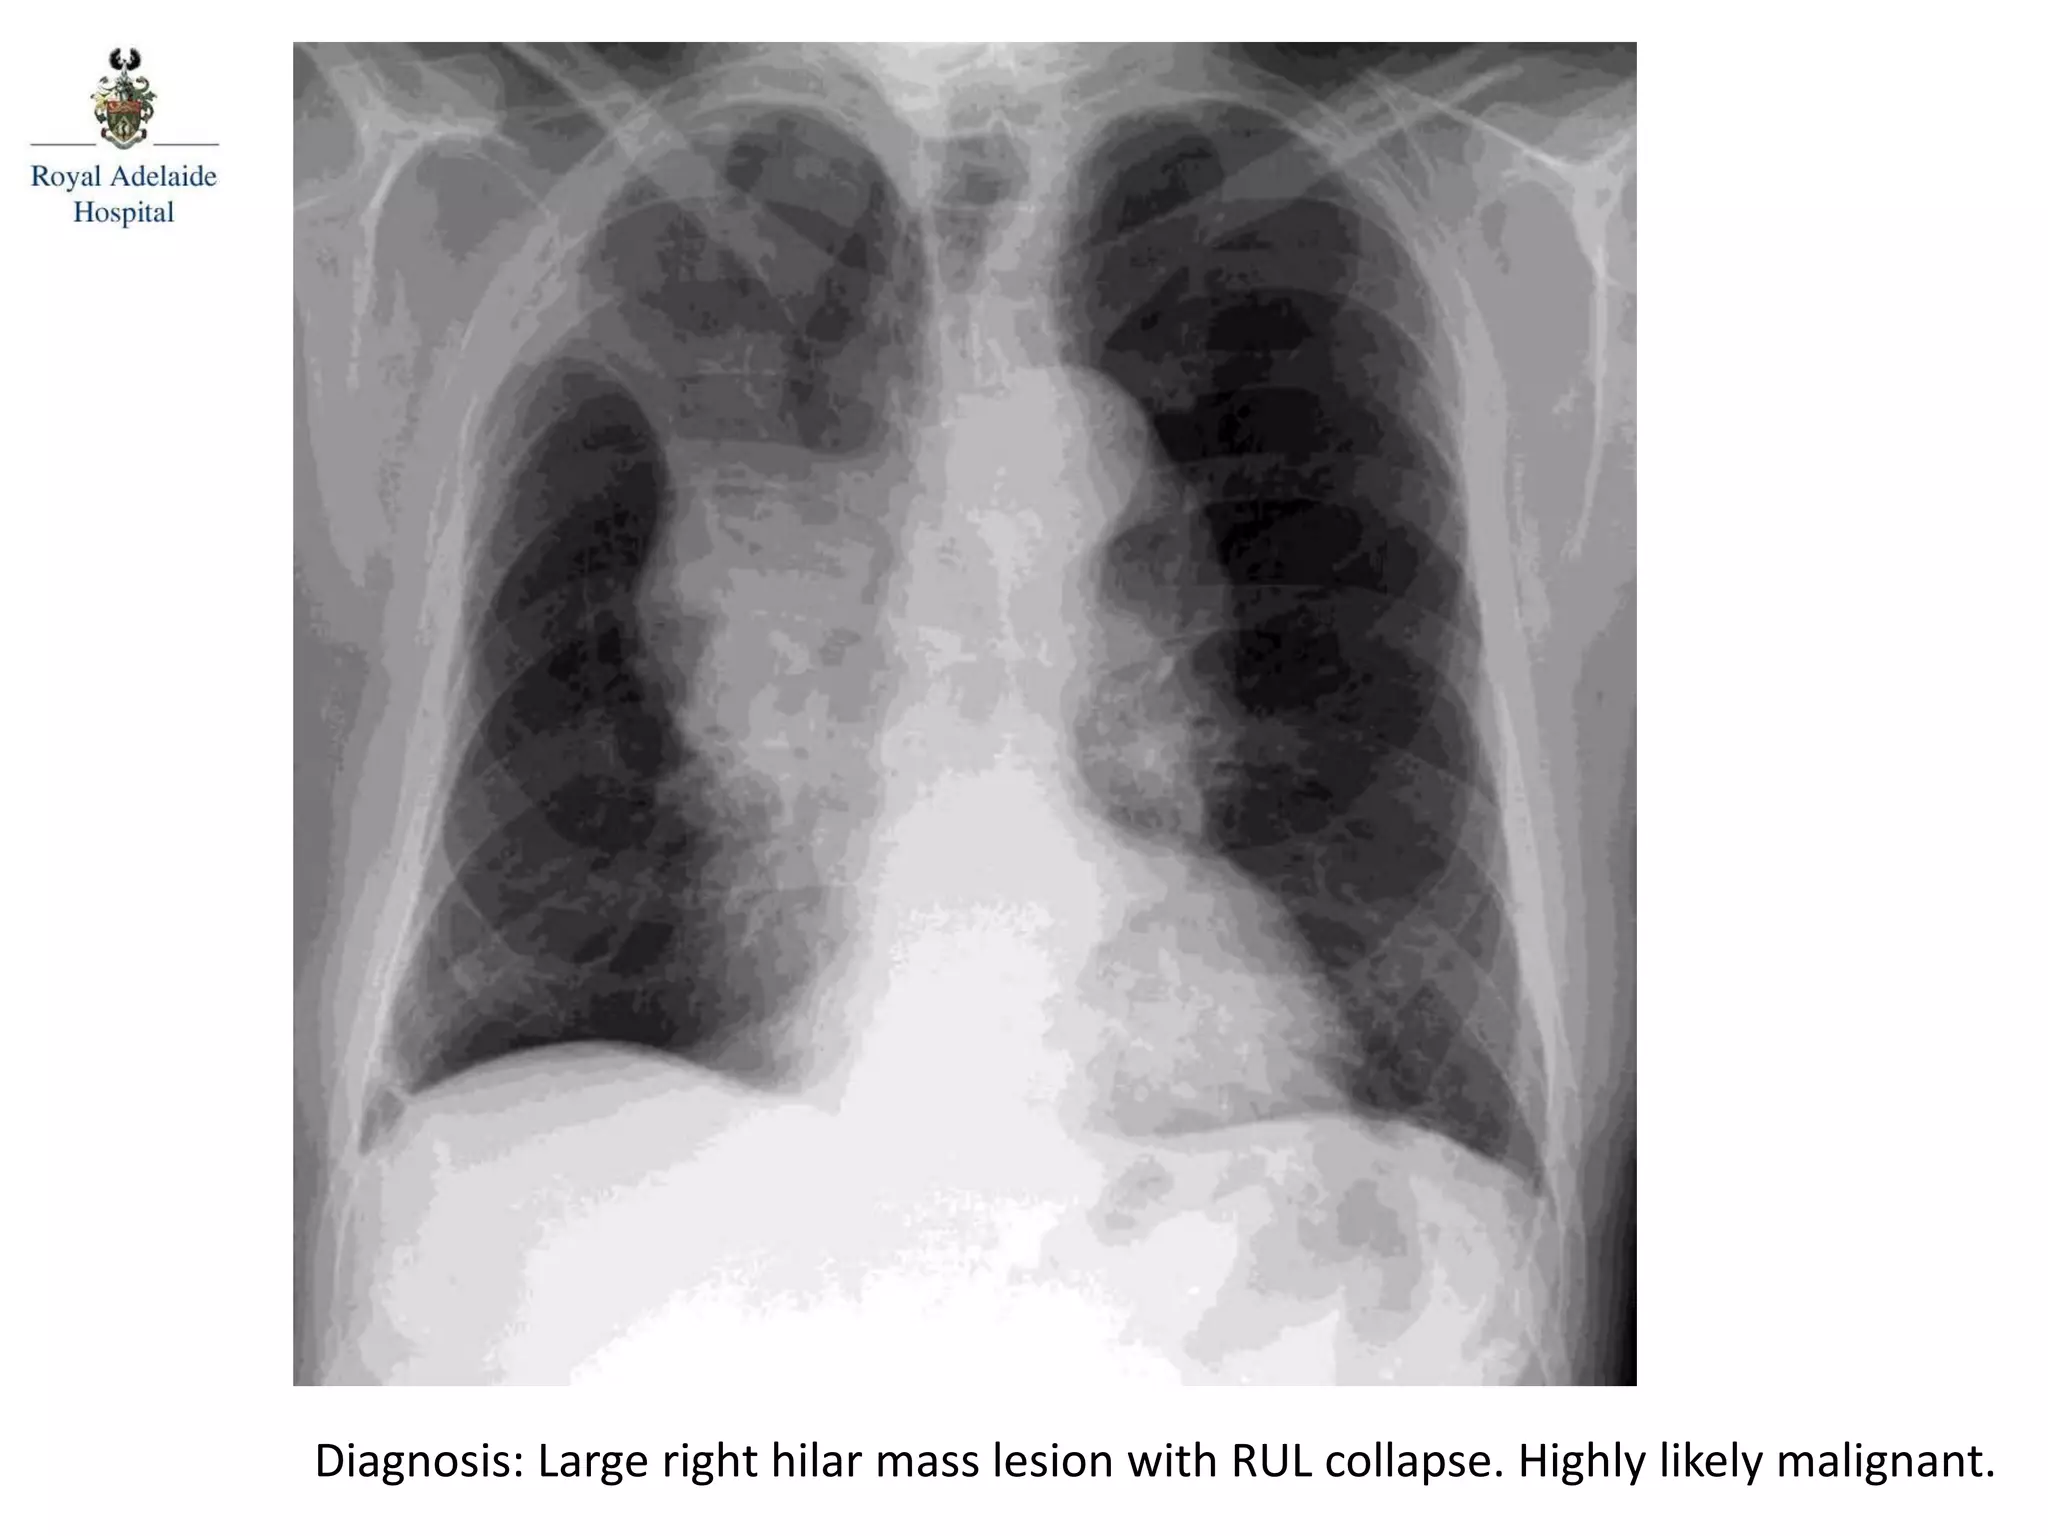

Diagnosis: Large right hilar mass lesion with RUL collapse. Highly likely malignant.